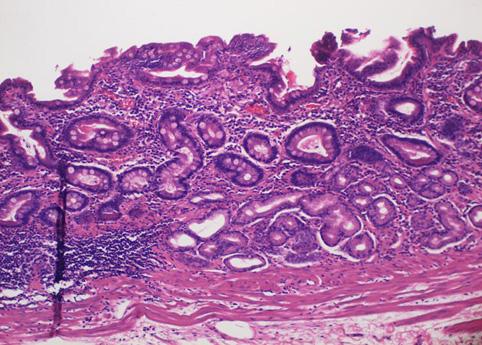

clasificación del pacienteTumor Epitelial Maligno/Adenocarcinoma

parte(separada por órganos)estómago(región)/cuerpo

método de exámenMicro

clasificación ectoscópica de tumoresTipo 0(tipo superficial)/Tipo IIb(IIb+III)

diámetro mayor del tumor40 -

grado de penetraciónm